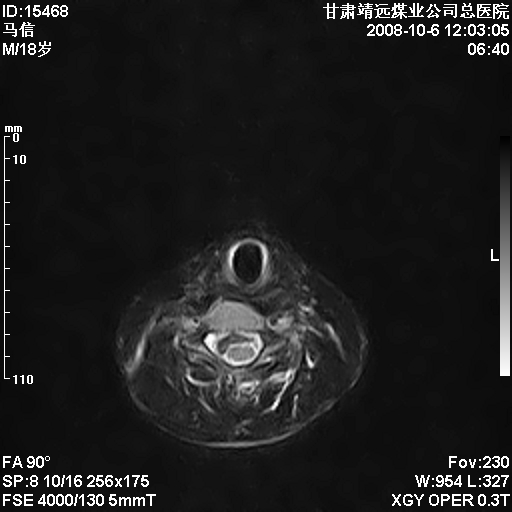

标题: MRI1827:颈椎内异常信号,是不是占位。

患者18岁,学生,在玩耍中受伤来检查,患者喜欢打篮球。颈椎内异常信号影,我们考虑占位,但是不像占位,又考虑硬膜囊的增厚,大家关建看颈椎椎管内的那个异常占位信号

脑脊液流动伪影?

后纵韧带增厚,颈2/3、3/4、4/5、5/6椎间盘变性、突出;椎体有旋转,提示椎小关节有问题;腰椎间盘变性,许莫氏结节。

是正常的脑脊液波动伪影

脑脊液流动伪影

你说的占位是伪影。在我们医院1.5t和3.0t的mr上是经常看见的。